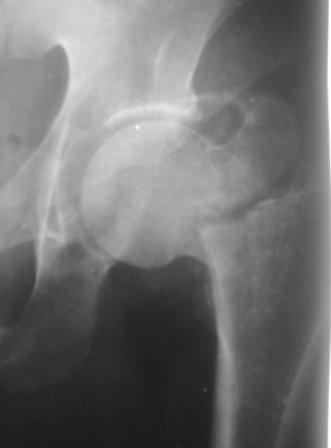

Уважаемые коллеги. Больной 1980г.р. после тяжелой сочетанной травмы от 03.12.10г: спленэктомии, ушивание разрыва печени, мн.переломы ребер. 05.02.11г операция по поводу спаечной к/непроходимости. И чрезвертельный перелом правого бедра, посмотрел под скопией сращения нет, при проверке двигается только дистальный отломок, а головка как бы припаяна к вертлуге. Укорочение ноги 5см, нога ротирована вовнутрь и приведена, из-за боли проверить объем движения не удается. В плане PFN -ChM , но может быть контрактура т/б сустава, или делать открытым способом (тогда большая кровопотеря, и так он ослабленный), м/б предварительно аппарат таз-бедро или вытяжение большим грузом? DHS ,blade plate кончились, имеется шеечные винты, Г-образные пластины ЦИТО-Бокачырева, и кое-что можно из пластин приспособливать по "гаражной ортопедии" От направления в НИИТО отказывается. Как нибудь надо помочь больному..... С уважением Абдурашид.

Как предлагали уважаемые коллеги, сегодня наложили спице-стержневой дистрактор таз-бедро, перед этим попробовали закрытую остеоклазию под в/в анестезией, движение в т/б суставе ( или в ложном суставе! ) восстановлен.

Р-снимки сразу п/о, следующий после дистракции, аксиальная - прощу извинения за плохое качество снимков.

Мне кажется надо еще продолжать постепенную дистракцию. И еще которая наверху шейки по моему это осколок от шейки, и она фиксирована оссификатом надвертлужной обл. Поэтому при повторной операции видимо придется открыто мобилизовать т/б сустав.